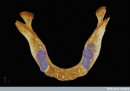

Martedì 11 marzo a Londra nel Regno Unito sono stati annunciati i vincitori dei Wellcome Image Awards 2014, i premi per le migliori immagini di scienza consegnati ogni anno dalla fondazione Wellcome, impegnata nella promozione della conoscenza sulla salute umana e degli animali. Le fotografie, realizzate in buona parte utilizzando microscopi, mostrano microrganismi marini, l’intricata rete di terminazioni nervose del cervello umano, embrioni di pesce e cristalli di semiconduttori. L’immagine che ha ricevuto una menzione speciale è stata quella del torace di un paziente cui è stato impiantato un cuore artificiale in attesa di un trapianto.

Dentro ogni foto, l’autore e qualche spiegazione sul soggetto.